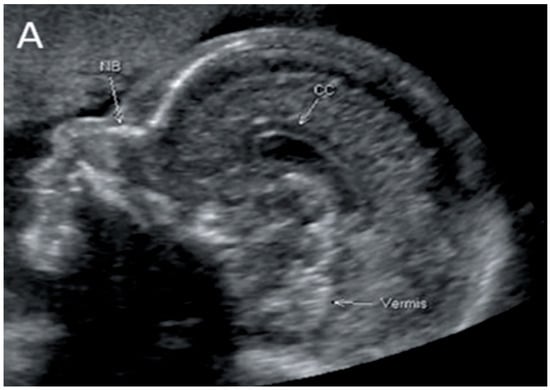

Figure 2.

Corpus callosum as captured by trans-abdominal mid-sagittal US scan at 23 weeks of gestation (A) and by mid-sagittal MRI scan at 33 weeks of gestation (B).